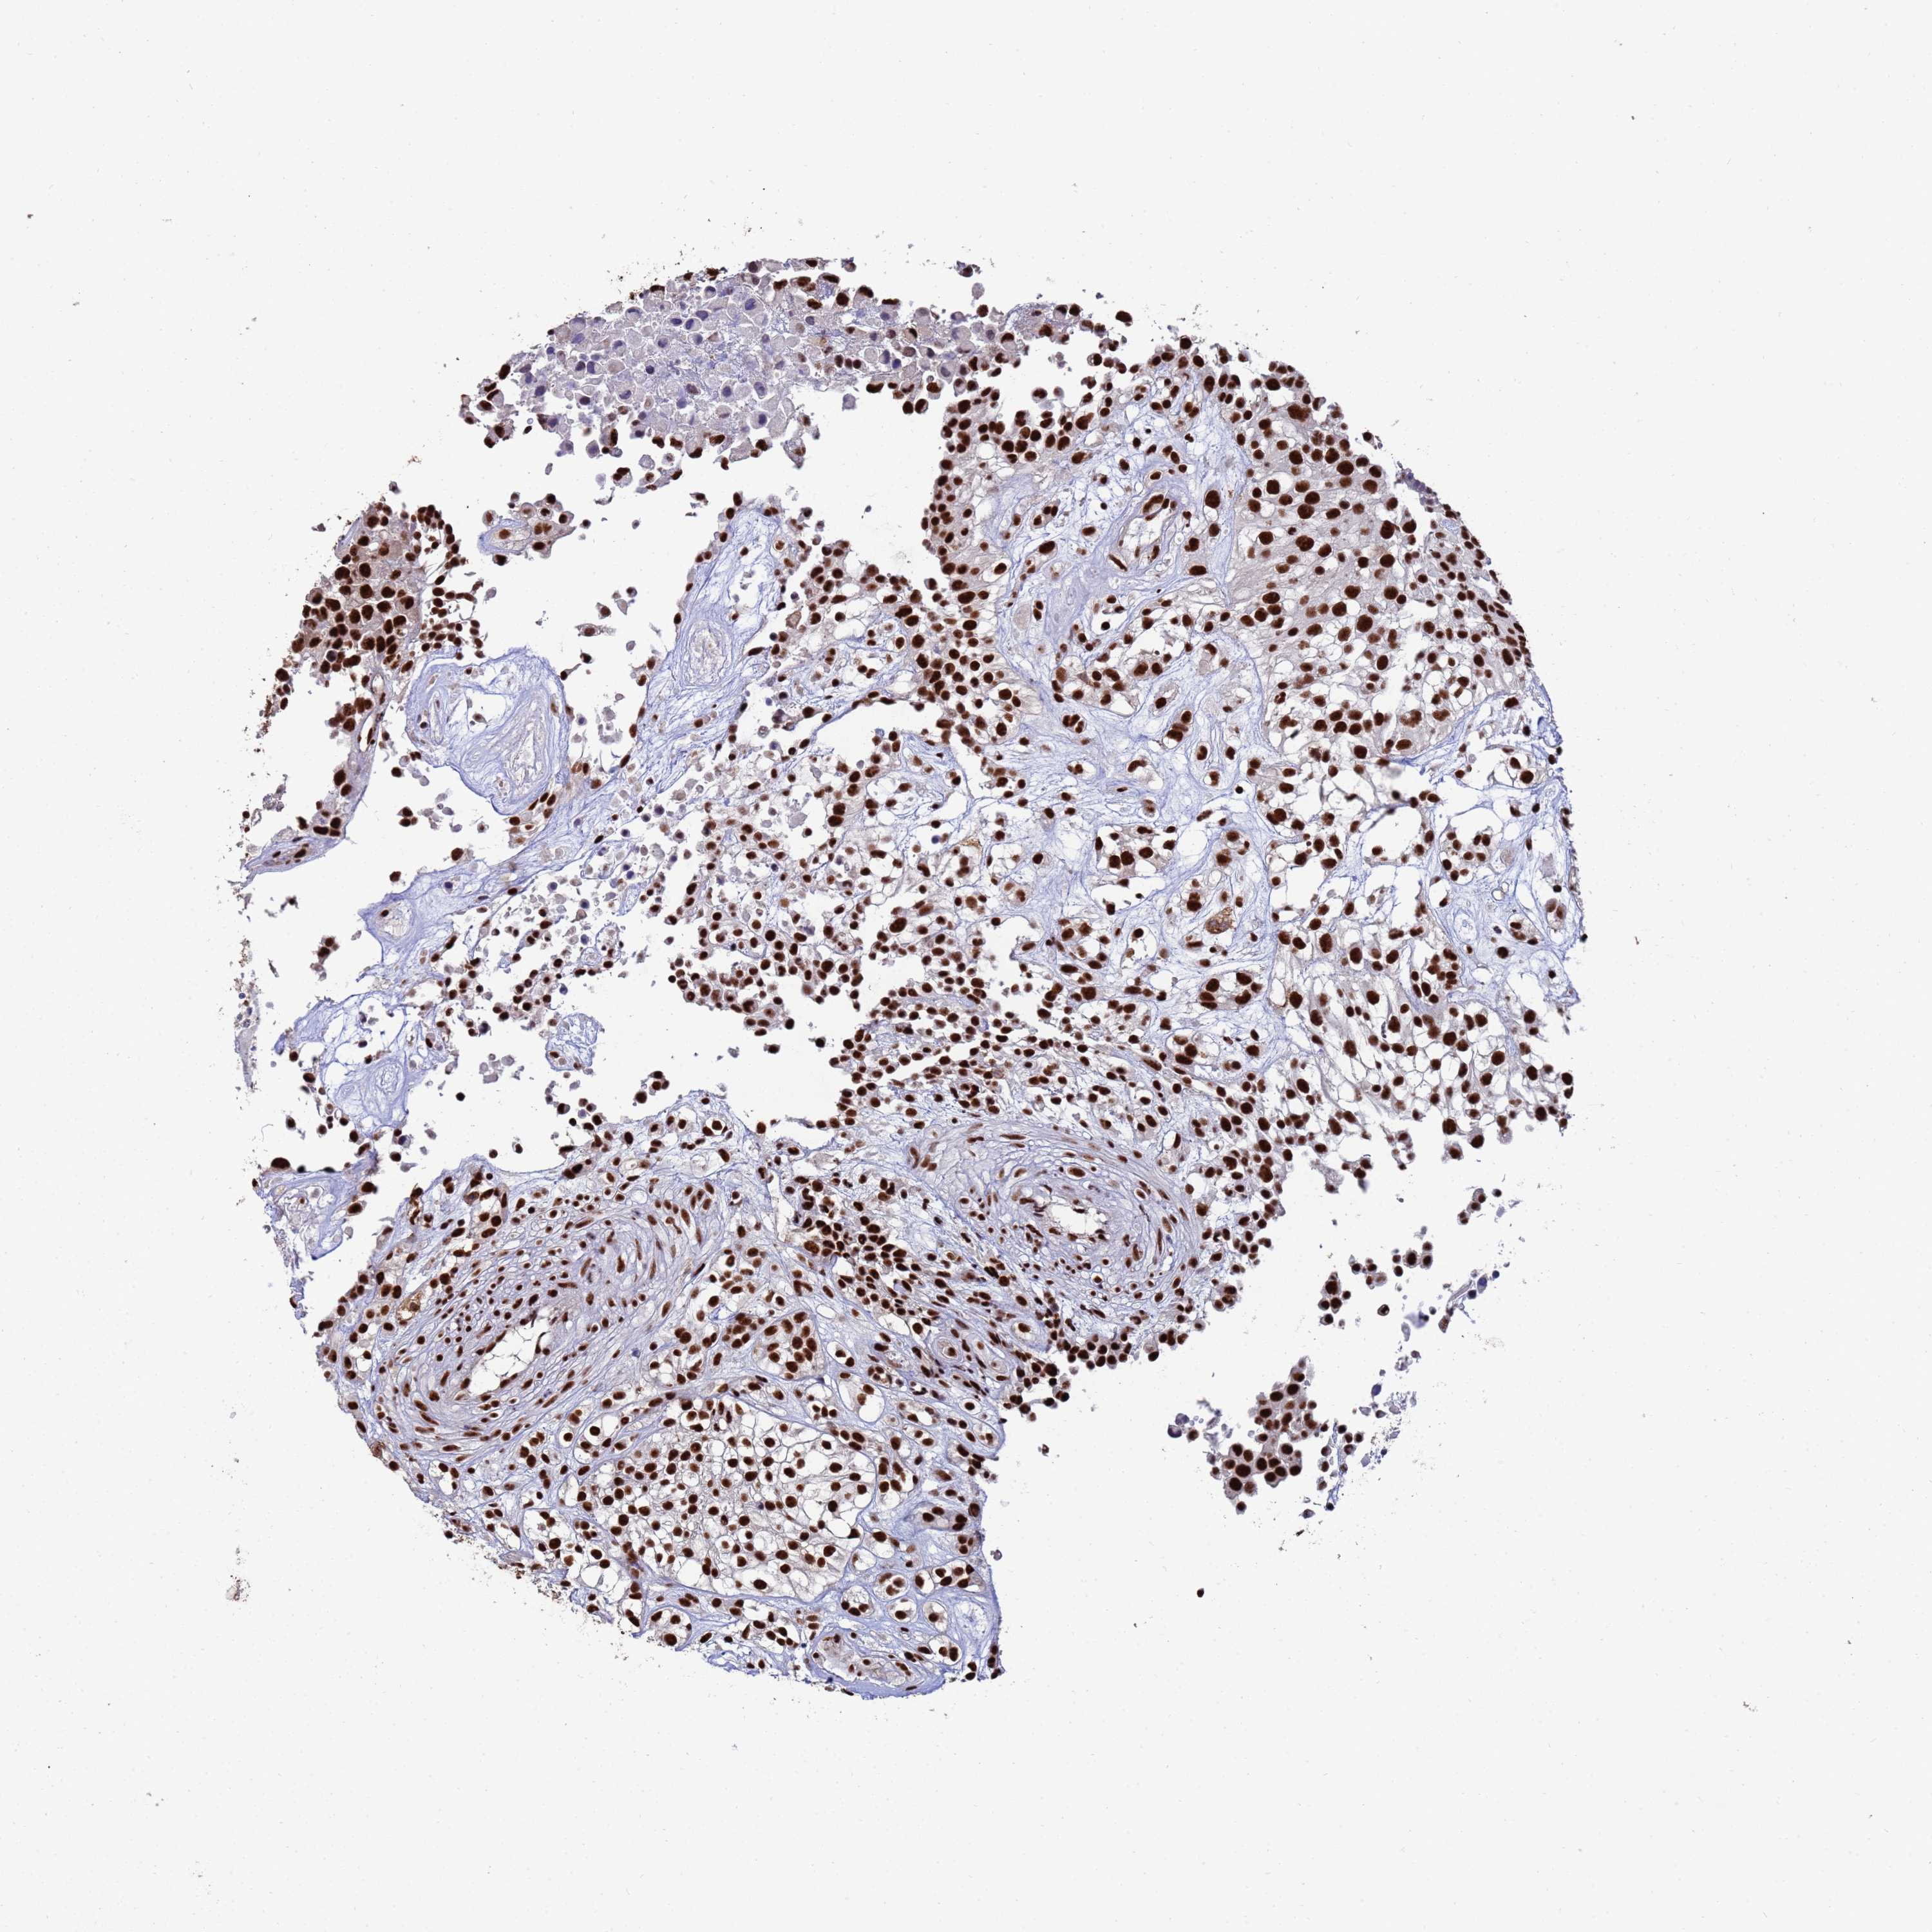

UROTHELIAL CANCER - Protein expressioni

A mouse-over function shows sample information and annotation data. Click on an image to view it in a full screen mode. Samples can be filtered based on level of antibody staining by selecting one or several of the following categories: high, medium, low and not detected. The assay and annotation is described here.

Note that samples used for immunohistochemistry by the Human Protein Atlas do not correspond to samples in the TCGA dataset.

Antibody stainingi

Antibody staining in the annotated cell types in the current human tissue is reported as not detected, low, medium, or high, based on conventional immunohistochemistry profiling in selected tissues. This score is based on the combination of the staining intensity and fraction of stained cells.

Each image is clickable and will lead to virtual microscopy that enables deeper exploration of all samples and also displays staining intensity scores, fraction scores and subcellular localization as well as patient and tissue information for each sample.

Antibody HPA045028

Staining

High

Medium

Low

Not detected

Intensity

Strong

Moderate

Weak

Negative

Quantity

>75%

75%-25%

<25%

None

Location

Nuclear

Cytoplasmic/membranous

Cytoplasmic/membranous,nuclear

Urothelial carcinoma, Low grade

Urothelial carcinoma, High grade

Urothelial carcinoma, NOS